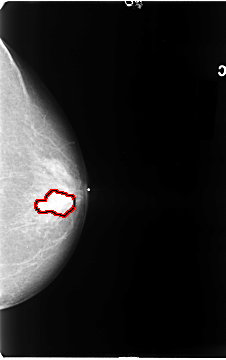

B_3088_1.RIGHT_MLO

FILE: B_3088_1.LEFT_MLO.OVERLAY

TOTAL_ABNORMALITIES 1

ABNORMALITY 1

LESION_TYPE MASS SHAPE LOBULATED MARGINS OBSCURED-ILL_DEFINED

ASSESSMENT 3

SUBTLETY 3

PATHOLOGY MALIGNANT

TOTAL_OUTLINES 1

BOUNDARY